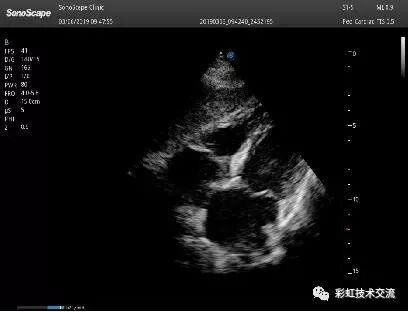

剑下四腔

(3)倾:整个超声探头平面紧贴受检区域皮肤,以超声探头与胸壁的接触点为支点,将超声探头前后倾斜,观察不同切面。